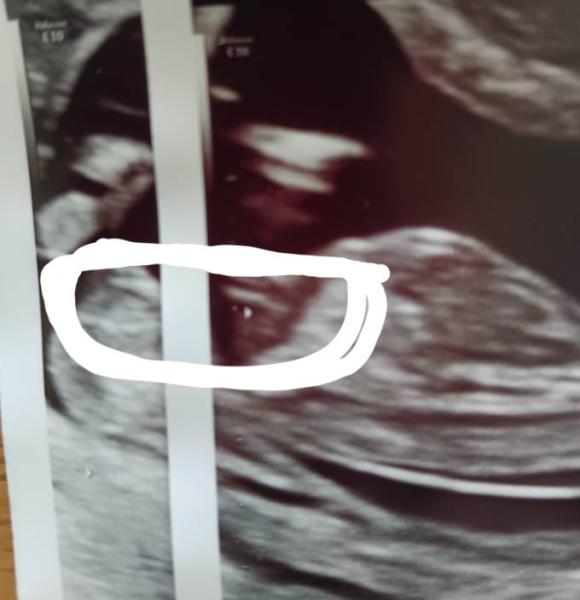

Hallo ihr lieben Ich habe erst am 05. Juni meinen nächsten gyn Termin und ich halte diese Wartezeit kaum noch aus ich bin soooo neugierig ob wir ein Brüderchen oder Schwesterchen für unsere Tochter bekommen Ich hab die Bilder Mal verglichen rechts das meiner Tochter und links das vom Baby im Bauch Was meint ihr? LG ina

Sieht für mich „gleich“ aus, nach Kaffeebohne und daher eher Mädchen, würde ich sagen.

Vielen Dank für die Antwort. Ich finde auch das es sehr ähnlich aussieht jetzt muss ich mich noch ein paar Tage gedulden und hoffen das man dann endlich das Geschlecht erkennt